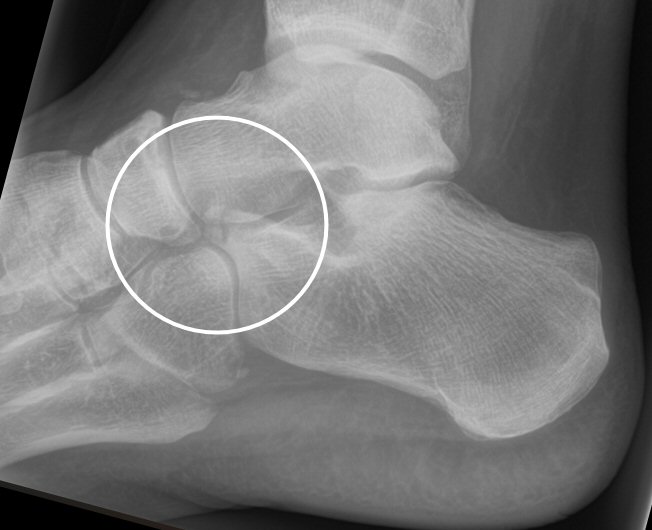

Fraktur i proc. anterior calcanei

Mindre avulsion av proc. anterior calcanei: gips med belastning 4 (vid litet fragment) till 6 veckor (större fragment), viktigt med fysioterapi med rörelseträning efter avgipsning. Kan ge långvariga besvär, man kan efter några månader injicera kortison i sinus tarsi. Vid ännu mer långvariga besvär kan man extrahera ev. löst fragment, men osäkert om det ger minskad smärta.